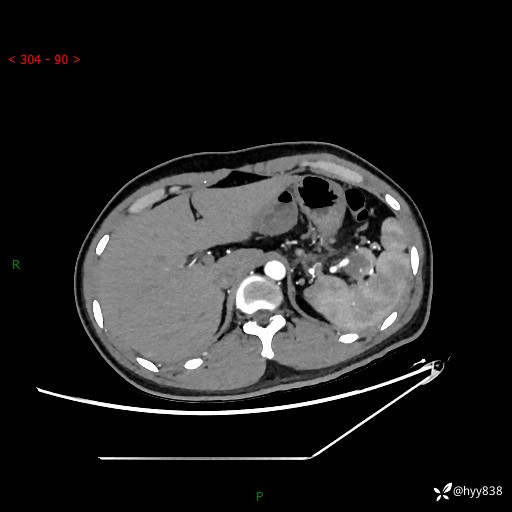

【患者信息】:31岁/男

【主诉】:间断性左下腹疼痛10天

【现病史及既往史】: 患者10余天前无明显诱因出现左下腹部疼痛,呈间断性,无恶心,呕吐,无黄疸,腹泻症状,于当地医院就诊,行腹部C提示:胰腺尾部占位。2型糖尿病。现患者为求手术治疗,门诊以“胰腺肿物”收入院。 患者起病来,一般情况可,大小便正常,体重体力未见明显减轻。

【检查】:胰腺CT平扫+增强